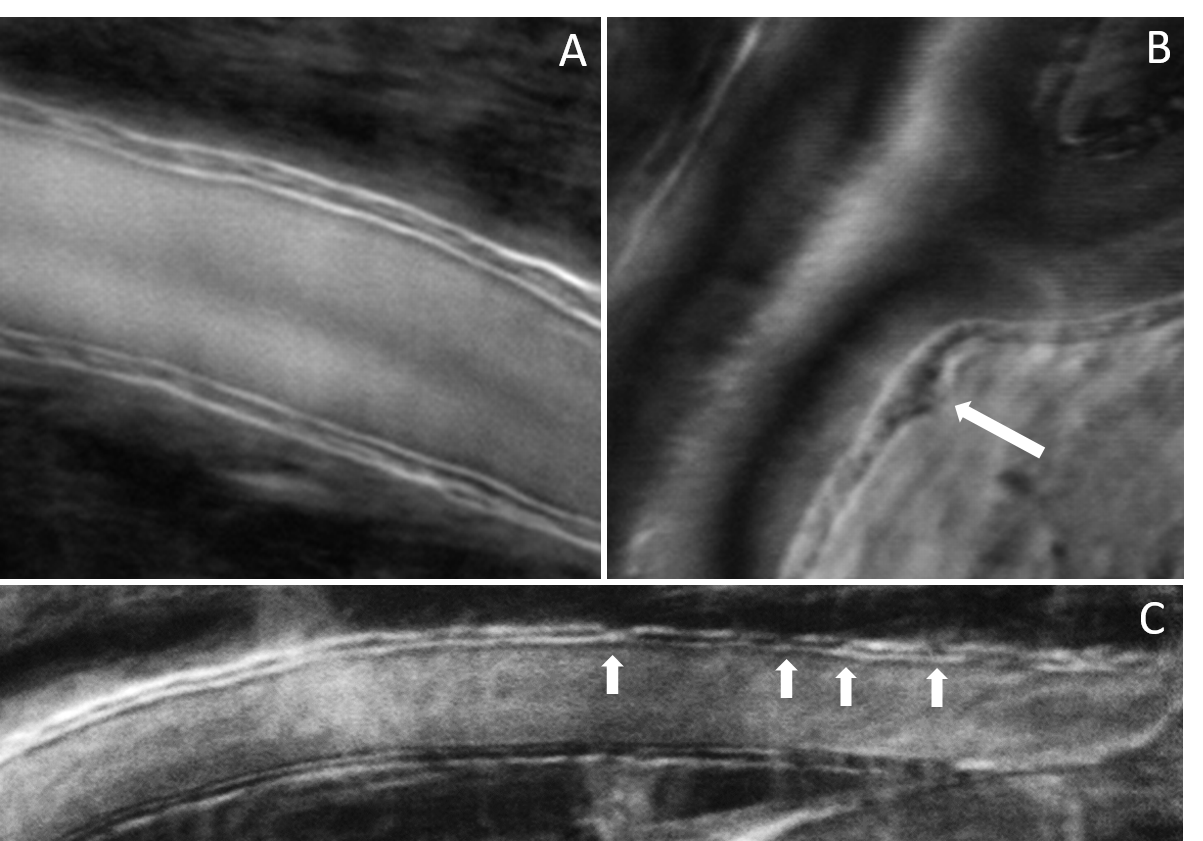

Vessel wall disruptions visualized with phase gradient imaging

“Cellular-Level Analysis of Retinal Blood Vessel Walls Based on Phase Gradient Images”, Diagnostics, 13(22), 3399, (2023)